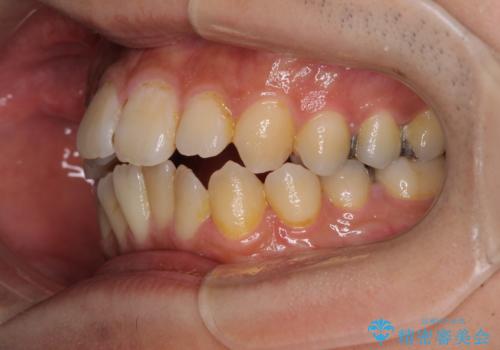

修復治療後に細かい部分をインビザラインで再度仕上げるプランとしました。

銀歯のセラミック治療が1番の希望であったため、ここまで歯列がきれいに整うとは思ってなかったようで、大変喜んでいただけました。